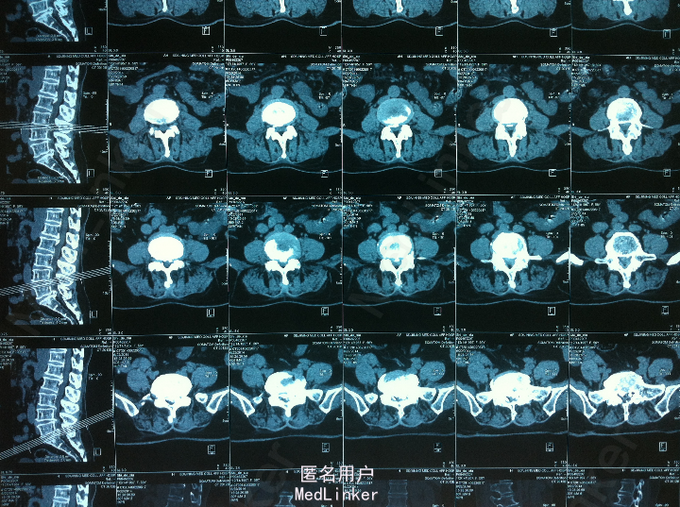

查体:腰部叩痛,腰部活动受限,左侧小腿外侧、足背感觉减退,左侧踝背伸、踇背伸、跖屈肌肌力4级,右侧踝背伸、踇背伸、跖屈肌肌力4-5级,双侧膝腱反射+,跟腱反射+,双侧巴氏征阴性。辅助检查: X-ray:腰椎退行性变节段性不稳。CT:腰椎间盘突出,腰3/4,4/5,腰5/骶1, MR:腰椎间盘突出,腰3/4,4/5,腰5、骶1椎间盘突出。